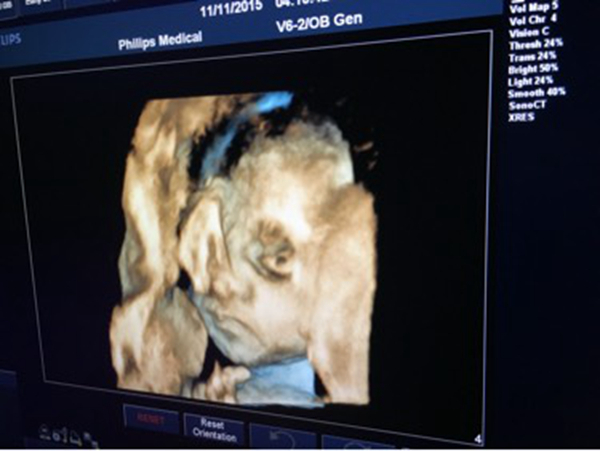

天生没有眼睛确实很让人烦恼,而无眼症应该是一种比较少见的基因疾病,这也是一种畸形即使查过b超也很难发现。专家认为该疾病可能是基因突变引起的,或者说孕妇在怀孕初期,胚胎发生了某些奇怪的变化,这些都是没办法解释的。

无眼症是一种很少见的疾病,有着很低的发病率,一些患儿缺少部分眼球,有些直接没有眼球,这种疾病很难通过B超发现。该患儿家人也说了产妇都坚持进行体检,都没发现什么不对劲的,没想到孩子会这样。